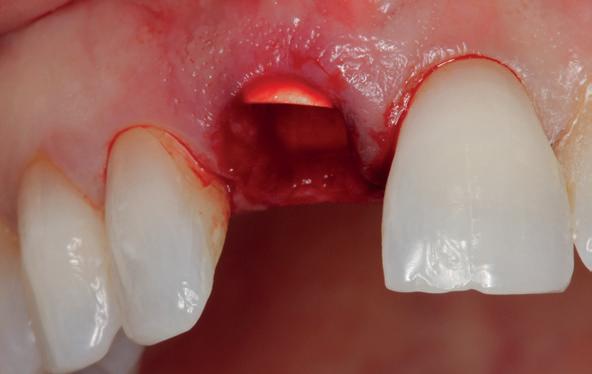

Implantologische behandelingen in het esthetische front vragen meer dan technische vaardigheid alleen. Ze vragen om overzicht, timing, vertrouwen en een team dat als vanzelf samenwerkt onder druk. Juist bij complexe casussen, waarin angst, infectie en hoge esthetische verwachtingen samenkomen, wordt zichtbaar hoe bepalend de rol van de tandartsassistent is.

Deze casus beschrijft een uitgebreide immediate implantaatbehandeling bij een patiënt die door meerdere collega’s werd geweigerd. Niet omdat de mogelijkheden ontbraken, maar omdat de complexiteit vroeg om een perfect afgestemde samenwerking. Het verhaal laat zien hoe de assistent in zo’n traject veel meer is dan een uitvoerende kracht of “mal”, maar een dynamische surgical guide die het proces mede stuurt, bewaakt en mogelijk maakt.De patiënt: wanneer alles samenkomt

Na het klinische onderzoek volgde het röntgenologisch traject. De CBCT liet precies zien wat we al vreesden: een front waarin het bot onregelmatig was, duidelijke radiolucenties rond de pijlers en een infectiegebied dat zich onder vrijwel de gehele brug had verspreid. Tegelijkertijd was er ook potentie. Net voldoende botstructuur om immediate implantaatplaatsing te overwegen, mits alles perfect gepland zou worden.